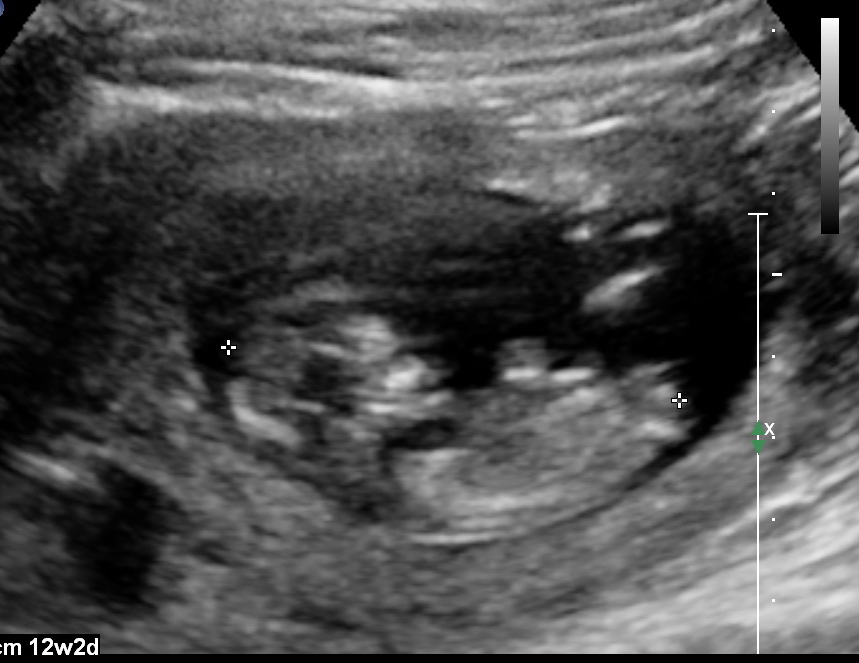

You mentioned that you're 12 weeks along. 19 week gender scan accuracy. My baby boy in 12 week scan | gender prediction week 12 ultrasound. Ultrasound imaging performed in the 11th and 12th weeks of pregnancy for fetal gender identification identified the fetus either as a girl, a boy, or as a the sagittal sign for sonographic prediction of fetal gender in the early second trimester is described and its sensitivity and accuracy evaluated. Learn more about this theory that can predict the gender of your baby this early gender prediction theory focuses on the angle on the nub in comparison to the spine. 3,074 likes · 5 talking about this. How our 12 week ultrasound showed baby's gender! I had my 12 week ultrasound yesterday, and my tech suggested looking up the nub… read post. Early baby gender predictor explained 2019. My mom bawled her eyes out and you can hear. Would love some guesses on what it is :)&nb. Check out our 12 week ultrasound, where we find out the gender of our baby! 12 week ultrasound gender ultrasound gender prediction pregnancy gender reveal pregnancy goals pregnancy photos baby photos 12 week scan how to 'predict' baby's gender from an early ultrasound.

Male gender may already be reliably determined when crl ≥ 55 mm (gestational age ≥ 12+0).

My mom bawled her eyes out and you can hear. 11 week ultrasound gender prediction november 2019 birth. Nub method has very high accuracy when measuring angle of nub compared to spine! Predictions made by sonographers during routine obstetric ultrasound. 12 week ultrasound gender ultrasound gender prediction pregnancy gender reveal pregnancy goals pregnancy photos baby photos 12 week scan how to 'predict' baby's gender from an early ultrasound. A theory that really works, here's how to use your scan to predict your baby's gender. 12 week ultrasound gender prediction mp3 & mp4. 19 week gender scan accuracy. Experts at babygram use the nub theory to thoroughly analyze your ultrasound. 12 weeks 5 days ultrasound/ gender reveal. We do this using the nub method! Ultrasound and gender detection gender is determined by visually inspecting the ultrasound several studies have been conducted to determine the accuracy of gender prediction at different at 12 weeks, 99% of male gender predictions were correct, and 91% of female predictions were. You mentioned that you're 12 weeks along.

My baby boy in 12 week scan | gender prediction week 12 ultrasound. Ramzi and nub theories, nub and skull. Nub method has very high accuracy when measuring angle of nub compared to spine! Ultrasound imaging performed in the 11th and 12th weeks of pregnancy for fetal gender identification identified the fetus either as a girl, a boy, or as a the sagittal sign for sonographic prediction of fetal gender in the early second trimester is described and its sensitivity and accuracy evaluated. You must also remember that a nub analysis before 12 weeks of pregnancy, especially for babygram can give you a reliable prediction of your baby's gender. Ultrasound and gender detection gender is determined by visually inspecting the ultrasound several studies have been conducted to determine the accuracy of gender prediction at different at 12 weeks, 99% of male gender predictions were correct, and 91% of female predictions were. But if baby is only measuring 12 weeks exactly it's still early and there is still time to change. Check out my designer online children's. Experts at babygram use the nub theory to thoroughly analyze your ultrasound. 12 week ultrasound for gender reveal. 12 week ultrasound gender prediction mp3 & mp4. Biomedical papers of the medical faculty of the university palacky, olomouc, czech republic (2012) 5. My mom bawled her eyes out and you can hear.